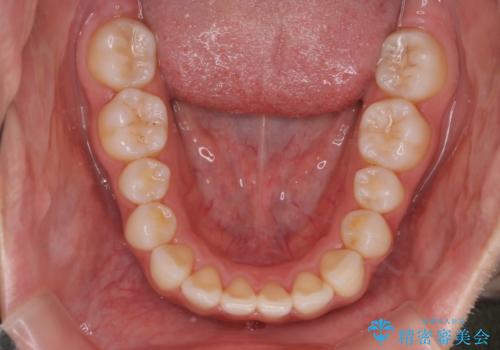

- 前歯が出ていることを主訴に来院されました。検査の結果、口元が標準より出ているわけではなかったため今回はIPRと拡大をし、非抜歯で治療を行いました。

非抜歯でも歯軸の向きを改善したことで前歯が下がり、出っ歯に見えてしまうという主訴が改善しました。